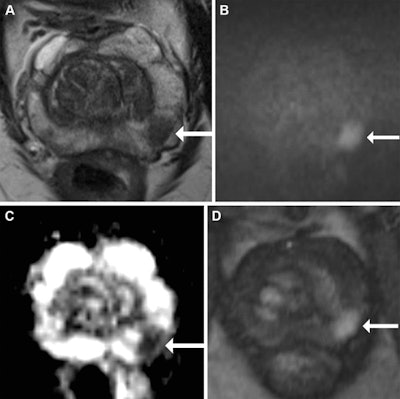

Multiparametric MRI in a 68-year-old male participant with a prostate-specific antigen level of 9.49 ng/mL. (A) Axial T2-weighted fast spin-echo MRI scan (repetition time msec/echo time msec, 3820/97) shows a 13-mm Prostate Imaging Reporting and Data System 4 nodule in the left midgland posterolateral peripheral zone (arrow). (B) Diffusion-weighted image (b = 1600 sec/mm2) and (C) corresponding apparent diffusion coefficient (ADC) map show marked restricted diffusion at the site (arrows), with an ADC of 515 µm2/sec. (D) Dynamic contrast-enhanced image shows focal early enhancement at the tumor site (arrow). Targeted biopsy revealed grade group 3 prostate cancer (PCa) with cribriform/intraductal histologic features. The participant underwent radiation therapy for treatment of PCa. Images and caption courtesy of Radiology.